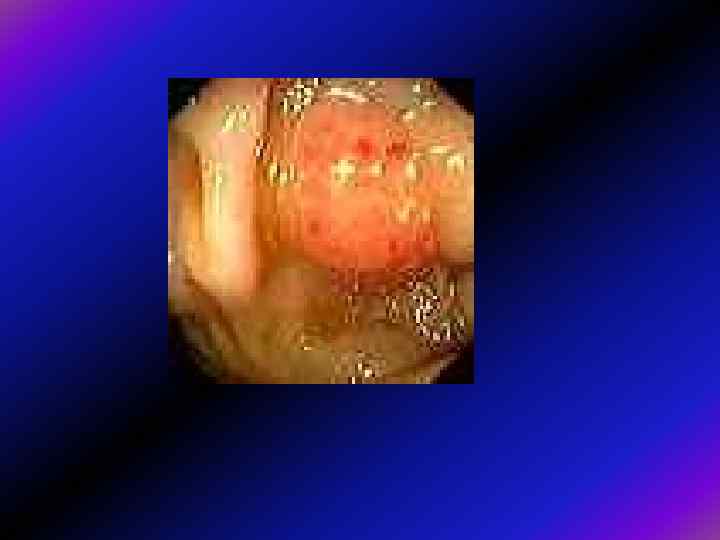

Візуальні особливості • Тубулярні аденоми, як вже зазначалося, частіше мають невеликі розміри, часто — ніжку, яка часом буває досить довгою. Головка поліпа, як звичайно, інтактна, дещо червоніша, ніж оточуюча слизова, гладенька або з часточковою поверхнею. Ніжка вкрита звичайною слизовою.

Вільозні аденоми, як звичайно, є утворами на широкій основі, що вкривають доволі велику ділянку слизової (англ. LST – пухлина з латеральним розповсюдженням). Через недостатнє кровопостачання вони виглядають блідими, поверхня їх зерниста, або нагадує цвітну капусту. Як звичайно, це дуже м'які і легко ранимі утвори.

Переважно екзофітний ріст (за Ганічкіним) Ганічкіним 1 А. Вузлова форма. Характерна наявність одного або декількох вузлів, розміщених на одній стінці. Поверхня їх горбиста, часто з виразкуванням на верхівці вузла, інфільтрація навколо вузла незначна, звуження просвіту немає. При інструментальній пальпації риґідність, при біопсії - фраґментація. 1 Б. Поліповидна форма. Сюди належать раки з поліпів, від поліпа візуально мало відрізняються. Верифікація переважно гістолоґічна. Карцинома невеликих розмірів, переважно має коротку ніжку, широку основу, поверхня частіше гладка, часом дольчата, можливо з виразкуванням на верхівці або при основі. Карцинома з вільозної аденоми має яскраво-червоний колір, поверхня нагадує мох. 1 В. Ворсиноподібна форма. Розростання у вигляді цвітної капусти червоного або пурпурного кольору, можливо з виразкуванням в центрі (кратероподібне), інфільтрацією стінки кишки, помірним звуженням просвіту. При контакті легко викликається кровотеча, при біопсії фраґментація.